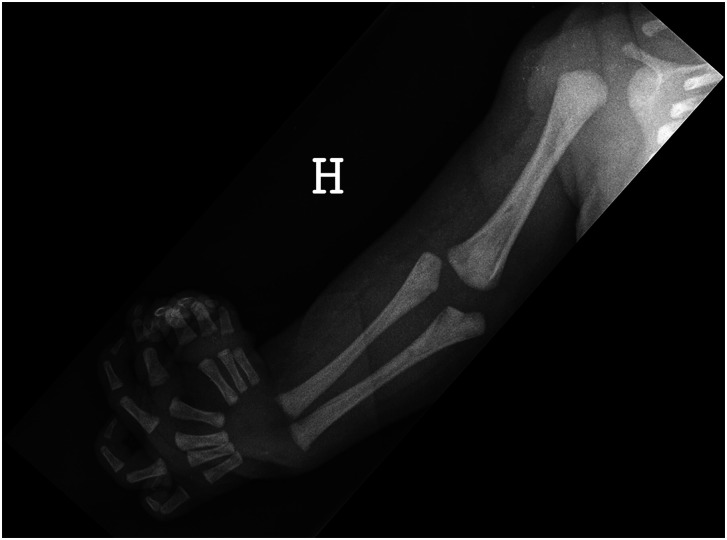

尺骨缺角是一种非常罕见的影响整个肢体的单侧先天性上肢畸形(CULA)。由于复杂性和多层次的累及,治疗仍然很困难。根据结构化的参数列表,对来自七个欧洲中心的24例尺骨重复,桡骨缺失和多指畸形进行了审查。首次问诊时,中位年龄为8个月(1-178),17例患者肩关节活动度良好,6例患者肩关节活动度较差,中位被动肘关节活动度为20°(0°-90°)。22/24例患者静息腕关节位屈曲。在拉伸和夹板后,肘关节手术包括11例患者的外侧近端尺骨切除术和6例患者的肌肉转移,分别改善被动运动和增加主动肘关节运动。8例患者进行了肌腱转移,23例患者进行了极化或伪极化。总体而言,患者术后表现出可接受的功能。提出了治疗这种严重CULA的指南。证据等级:四级。

Ulnar dimelia is a very rare unilateral congenital upper limb anomaly (CULA) affecting the whole extremity. Treatment remains difficult because of the complexity and multi-level involvement. Twenty-four cases with duplicated ulna, absent radius and polydactyly from seven European centres were reviewed according to a structured list of parameters. At first consultation, median age 8 months (1-178), the shoulder movement was good in 17 patients or poor in six, and the median passive elbow range of motion was 20° (0°-90°). The resting wrist position was flexed in 22/24 patients. Following stretching and splinting, elbow surgery included resection of the lateral proximal ulna in 11 patients and muscle transfers in six to improve passive movement and increase active elbow motion, respectively. Tendon transfers were performed in eight wrists and a pollicization or pseudo-pollicization in 23 patients. Overall, patients demonstrate acceptable function postoperatively. Guidelines for treatment of this severe CULA are presented.Level of evidence: IV.